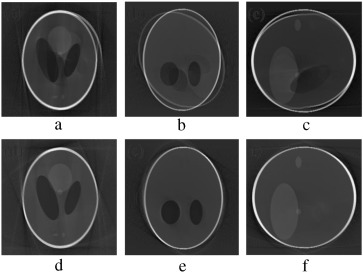

In the second stage of verification, the performance of our proposed marker-based estimator is tested with all the abrupt motion-corrupted cases of Figure 7 , Figure 8  and Figure 9 . Simulation results of actual and estimated motion parameters are listed in Table 6 , Table 7  and Table 8 . Estimated translation motion parameters are within 1.5% of actual values, and estimated rotational parameters are within 0.1% of actual values. Now, to demonstrate the efficacy of our proposed artifact mitigation technique, we apply the estimated motion parameters to the back-projection stage of the MB_FDK algorithm to reconstruct the 3D volume from the above different cases of motion corrupted projection data sets. In Figure 14 , Figure 15  and Figure 16 , we plotted the axial, coronal and sagittal slices taken from the reconstructed volume of different gradual rotational motion corrupted cases and motion artifacts compensated cases, side by side. From these figures, it can be observed that the motion artifacts originated from the gradual variations of motion have significantly been reduced by the MB_FDK approach. In Figure 17 , Figure 18  and Figure 19 , we plotted the axial, coronal and sagittal slices taken from the reconstructed volume of abrupt motion corrupted cases and motion artifacts compensated cases, side by side. From these plots it can also be inferred that the MB_FDK approach has significantly reduced the motion artifacts originated from the abrupt and large variations of motion.